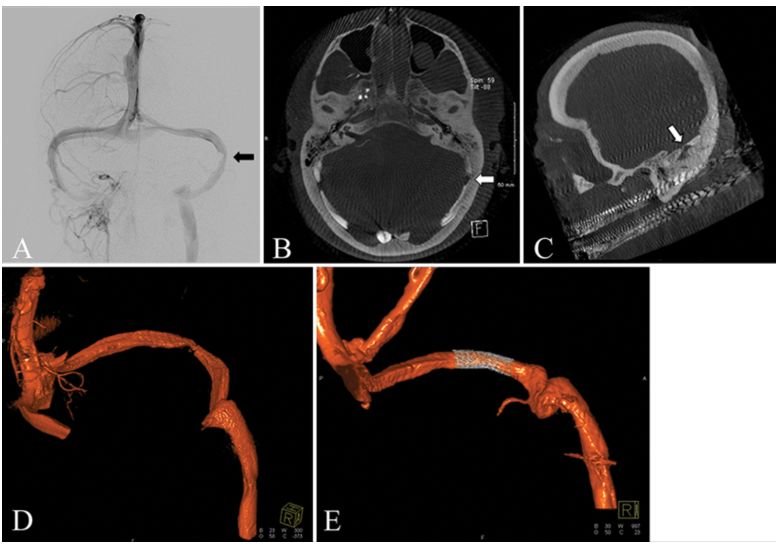

13.椎动脉夹层动脉瘤行血管内弹簧圈栓塞治疗后发生延髓梗死的预测因素。

Predictive factors of medullary infarction after endovascular internal trapping using coils for vertebral artery dissecting aneurysms.

PMID: 28799869 DOI: 10.3171/2017.2.JNS162916

椎动脉夹层动脉瘤(vertebral artery dissecting aneurysms, VADAs)首选血管内弹簧圈栓塞治疗,但有发生延髓梗死的风险。研究纳入100例血管内弹簧圈栓塞的椎动脉夹层动脉瘤患者,30例发生延髓梗死,其中27例为延髓后外侧,3例为延髓前内侧。对延髓梗死患者进行临床分析,结果显示:栓塞长度并非延髓梗死发生的危险因子,而是夹层动脉瘤所在的解剖位置。栓塞VA远端动脉瘤发生的延髓梗死的风险低,但患者的症状重;保护脊髓前动脉的起始部可以降低延髓梗死风险;栓塞的长度越短,发生并发症的可能性就越低,但仍不能防止梗死的发生。对于存在严重缺血并发症的破裂型VADAs(如对侧VA发育不良、病变累及小脑后下动脉或脊髓前动脉不适宜栓塞治疗)或未破裂型VADAs者可以考虑血管重建治疗。

【祝海平】